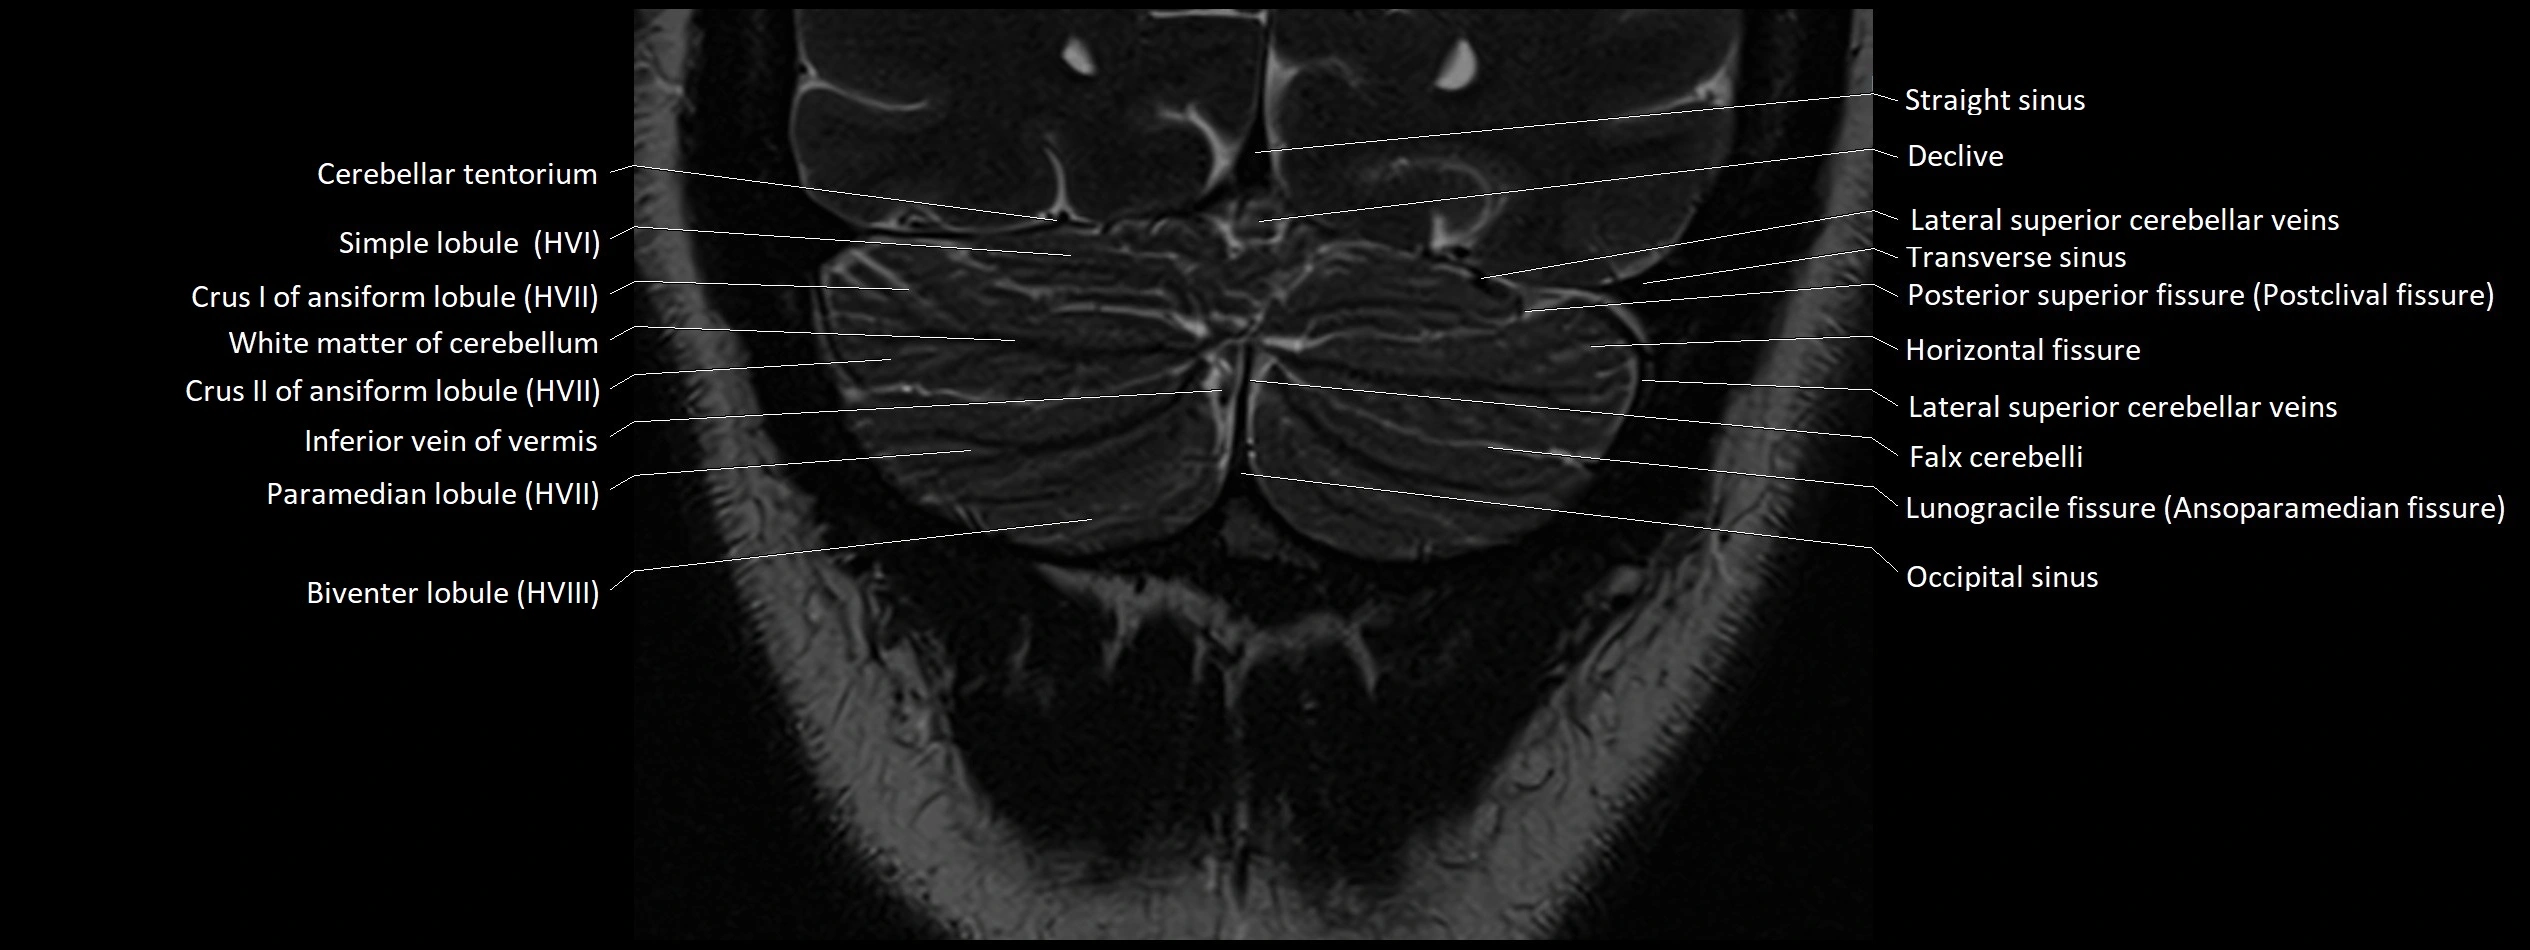

MRI images